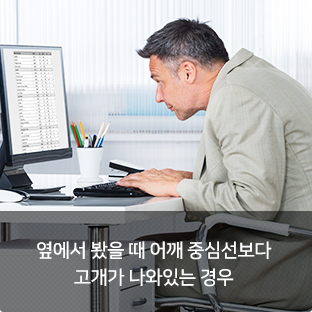

위 증상 중 한가지라도 해당된다면 “거북목”일 수 있습니다.

장시간 구부정한 잘못된 자세로 목이 앞으로 빠지면서 일자목 형태가 되는 증상을 말합니다. 모니터, 스마트폰을 장시간 사용하는 현대인들에게 가장 많이 발생되는 통증 질환입니다.